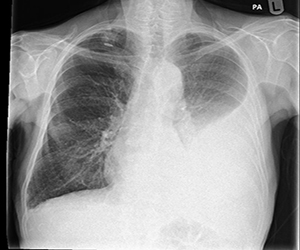

Pleural effusion is accumulation of fluid around (not inside) the lungs. Most common causes include infections like tuberculosis, pneumonia; heart failure, kidney disease, cancer etc

• Chest X-ray